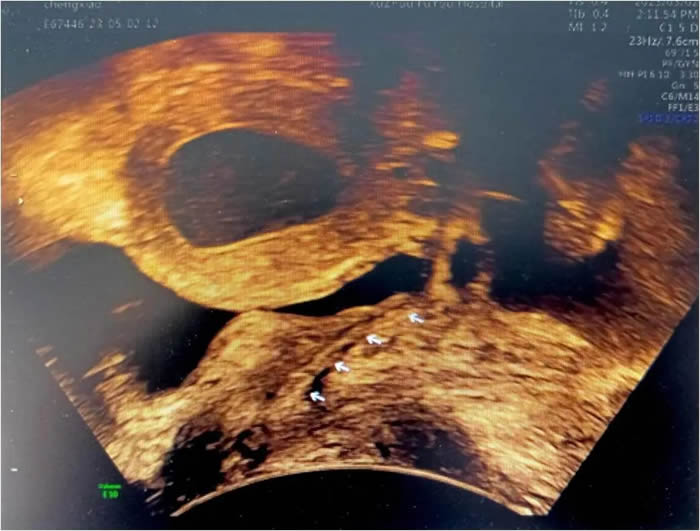

小玲(化名)13歲,到徐州市婦幼保健院就診時,周期性腹痛已持續(xù)一年之久,不僅影響了孩子的學業(yè)、整個家庭也陷入了無限的困境。經(jīng)各項檢查發(fā)現(xiàn),小玲患有先天梗阻性生殖道發(fā)育異常,先天性無陰道和條索狀宮頸。雖然如此,小玲的子宮卻發(fā)育良好,所以每次月經(jīng)來潮時,經(jīng)血無法正常排出,只能通過輸卵管逆流到盆腔,導致難以忍受的腹痛。小玲也曾在父母的陪同下到國內(nèi)多家大醫(yī)院就診,給出的治療方案均是切除子宮體,等待時機做二期陰道成形手術(shù),這對于一個13歲的女孩,還有父母來說是難以接受的。

早在進行前期檢查時,李教授就發(fā)現(xiàn)小玲一側(cè)輸卵管因經(jīng)血逆流造成嚴重積水傘端封閉,已失去了保留價值。如果能將積水的輸卵管休整后移植到子宮下端代替宮頸管,便能變廢為寶。但國內(nèi)、外關(guān)于先天性陰道、宮頸發(fā)育異常的Ⅱ型陰道閉鎖保留子宮的手術(shù)成功案例十分罕見,可參考的資料更是少之又少。國內(nèi)、外文獻檢索亦未見有使用輸卵管代替宮頸管的案例報道,也是李桂林教授團隊在醫(yī)學未知領(lǐng)域的又一次“創(chuàng)新之旅”。

在獲得家屬知情同意后,2023年4月底,通過腹腔鏡方式,李桂林教授團隊截取了3公分有血供和功能的輸卵管,成功為小玲實施了輸卵管代宮頸管+陰道成型重建手術(shù)。成為醫(yī)學史上,國內(nèi)、國際第一例成功實施該方案的病例。